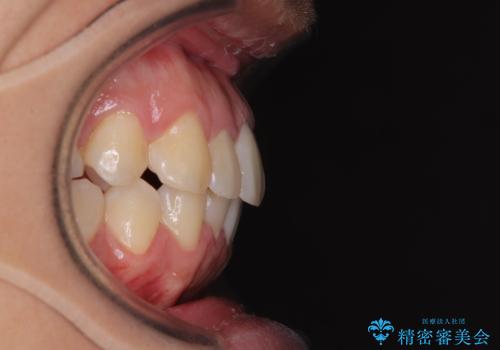

前方に捻れた前歯を治したい インビザライン矯正治療

- 前歯のデコボコを治したいとのことで来院された患者様です。

上下顎ともに歯列全体の後方移動とIPR(歯と歯の間を削る)によってデコボコが解消するように設計し、インビザラインにより治療を行うこととしました。